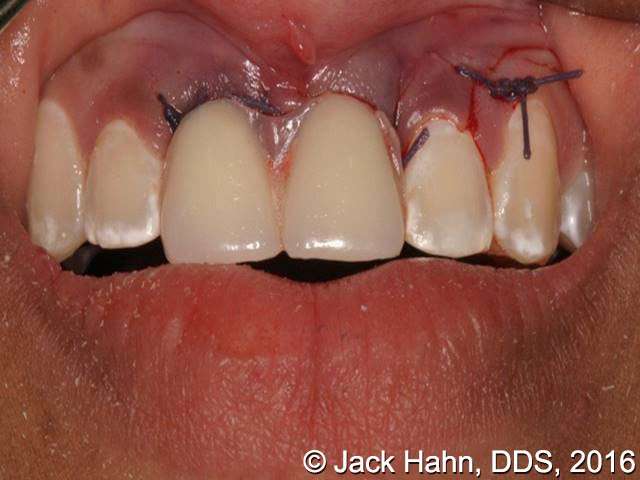

CASE #4 Trauma Case – Central Incisors Internal / External Resorption

Implants, that replace failed endo- or perio-compromised teeth, have a MUCH higher success rate with laser decontamination of the osteotomy site. LightScalpel laser surgical and perio laser tips ensure excellent access to extraction socket for the optimum removal of granulation tissue and socket decontamination (protocol involves manual curettage of the socket with alternating rinsing and lasing).

The patient, a 17-year-old female was involved in a water slide accident 3 years ago. As a result, both central incisors were avulsed and an endodontist replanted them. Both teeth exhibited internal and external resorption. Dr. Hahn extracted both central incisors, removed all the root fragments and sanitized the sites with the LightScalpel laser which also eliminated any granulation tissue. The #8 area was prepared to place a Hahn 4.3×13 Implant and #9 was prepared for a Hahn 3.5×13. 3mm tall Hahn healing abuts were placed slightly below the gingival-tissue level to help develop an emergence profile when at the restoration time in 4 months. Upon seeing the x-ray, Dr. Hahn tightened the healing abutment on #9 to be sure that it was completely seated on the implant. 45nucm. stability was achieved on both implants. He then placed some bone putty to seal any openings. To be on the safe side, he decided to place a temporary partial instead of immediate temporary prosthetics.